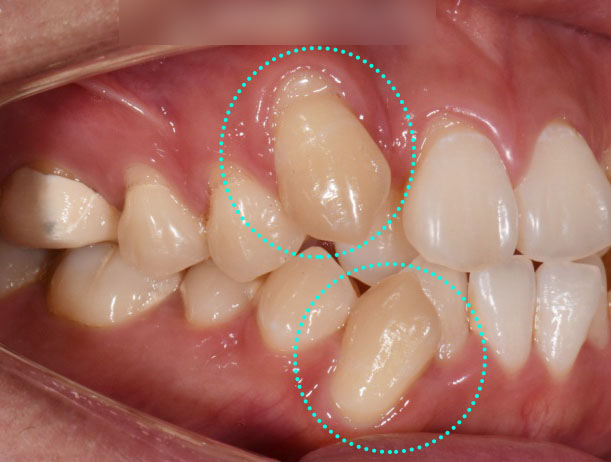

1. 치열이 빼뚤빼뚤하고

덧니가 도드라져 보여요.

가지런하지 못한 치열과 더불어

도드라져 보이는 덧니를

개선하고 싶어 하셨는데요.

이는 맹출 이상치로

정상적인 위치에서 벗어나거나

겹쳐서 나는 치아를 의미합니다.

종종 이렇게 턱이 작아 공간이 부족하거나

과밀한 경우에 생길 수 있습니다.